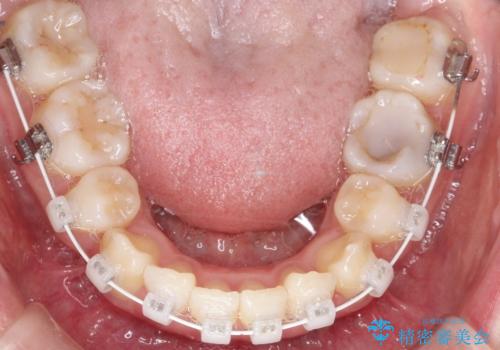

- ハーフリンガル

- 2年1ヶ月

目立たない装置をご希望でしたので、上下左右の歯を1本ずつ抜歯してハーフリンガルでの矯正を行いました。